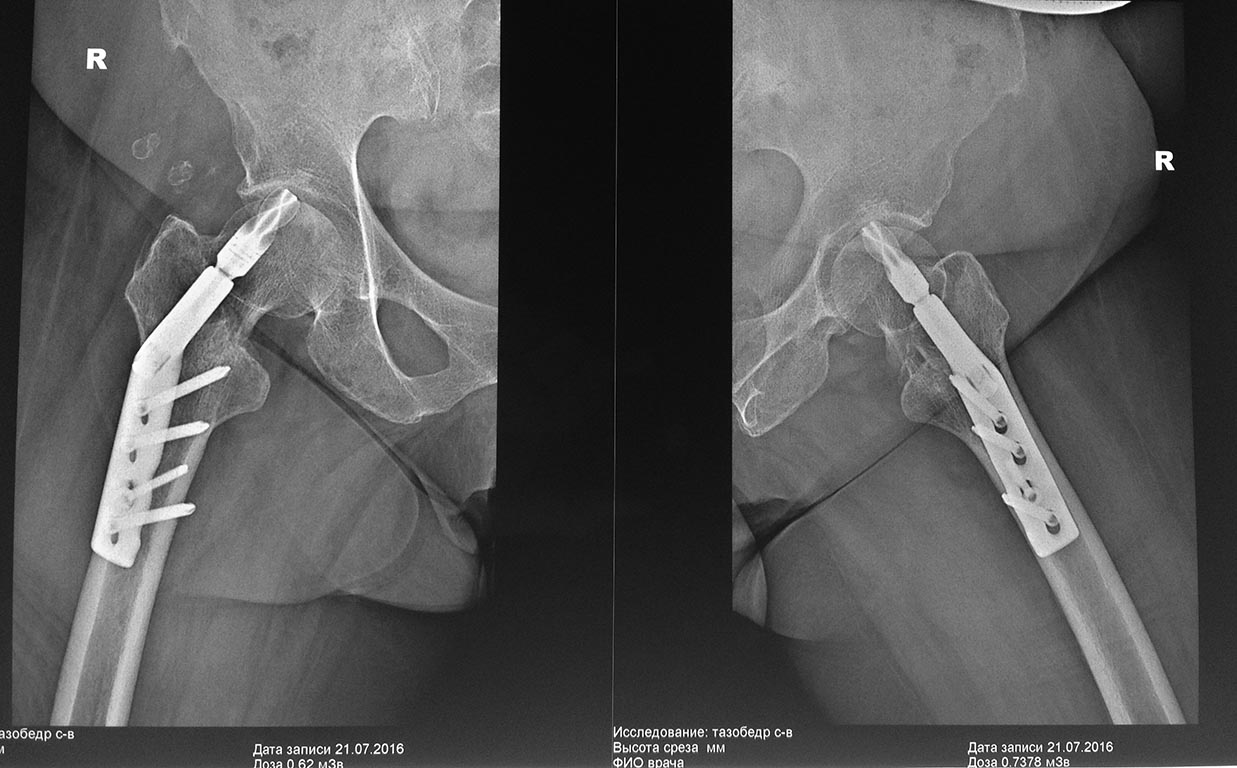

Добрый вечер уважаемые коллеги. На консультацию обратилась пациентка 62 лет с жалобами в области правого тазобедренного сустава, хруст и ограничения движения в суставе.

Из анамнеза : 12 апреля 2016 года упала дома на область правого тазобедренного сустава, доставлена в больницу, где больной было наложено скелетное вытяжение, а 14 апреля 2016 года выполнена операция - остеосинтез правого бедра, конструкция DHSA (Китай). Полтора-два месяца находилась в горизонтальном положении, затем вертикализирована, начала передвигаться при помощи ходунков с возрастающей нагрузкой на оперированную конечность.

21 числа больной выполнен рентген контроль, больная отправлена на консультацию к оперирующему хирургу, которым рекомендовано продолжить возрастающую нагрузку и разработку движения в суставе. Больная обратилась вновь ко мне на консультацию. Из анамнеза : около 12 лет нет месячных, около 30 лет проживает в условиях крайнего севера, 3 года принимает бивалос по интересной схеме - по 1 пакетику в течение месяца 1 раз в год, Бонвива по 1 таблетке 1 раз в месяц в течение 2 лет. Страдает двухсторонним Гонартрозом 3 степени. Передвигалась при помощи трости испытывала ограничение движений больше в правом коленном суставе, хромоту.

Теперь по сути. Не достигнута репозиция - не устранена наружная ротация дистального отломка, длина не восстановлена. Шеечный винт (helical blade) коротковат и введен кпереди. Соответственно, уже есть cut-out. Вариантов два - удаление и эндопротезирование (оптимально) или удаление и реостеосинтез в надежде, что площадь оставшегося неповрежденным хрящевого покрова позволит суставу "выжить".